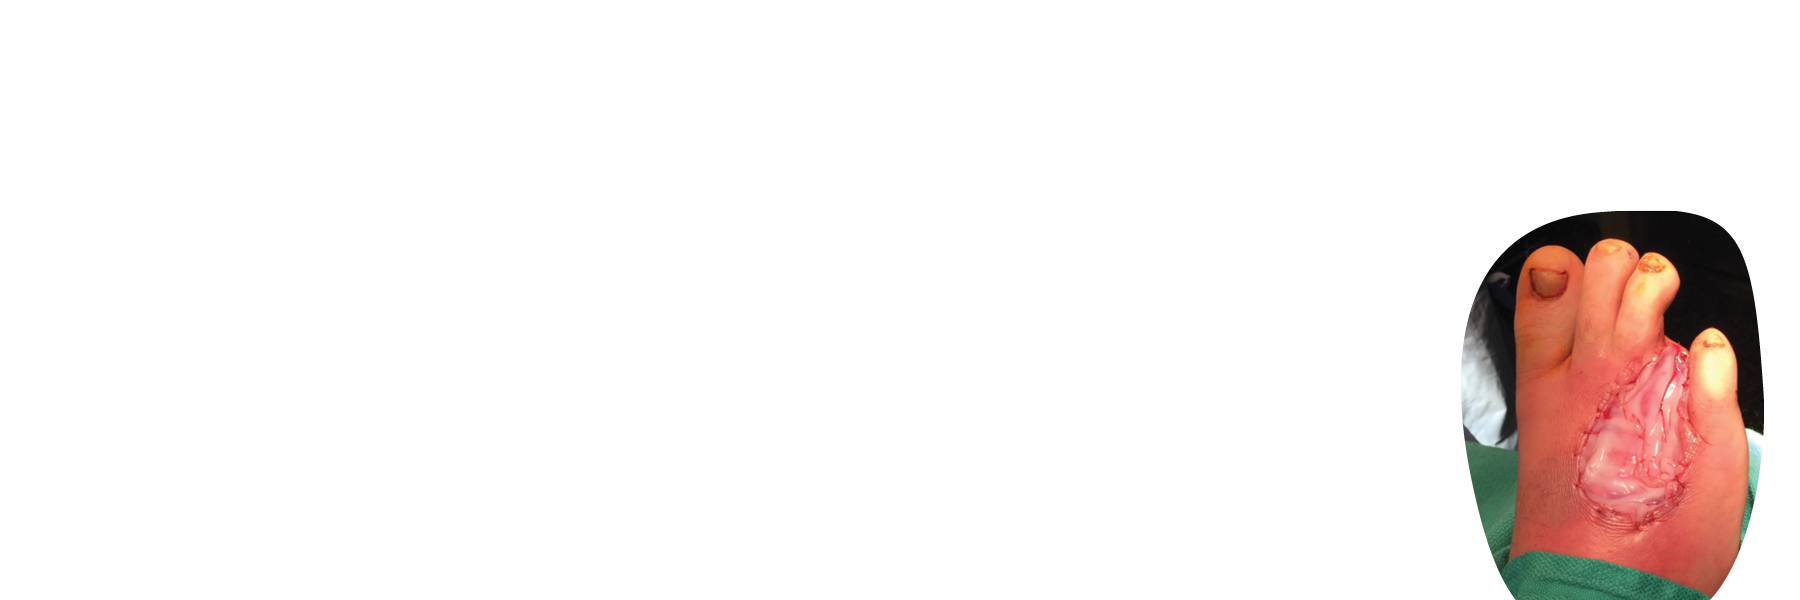

STRAVIX Tissue is a robust, easy-to-handle graft that sutures easily, conforms intimately, and performs across specialties*, from podiatric wounds to complex soft tissue reconstruction.1

GRAFIX XC Tissue brings the full power of human placental tissue—native cells and an intact extracellular matrix—directly to the wound bed.3,4

*Can be used as a wrap, cover, or barrier